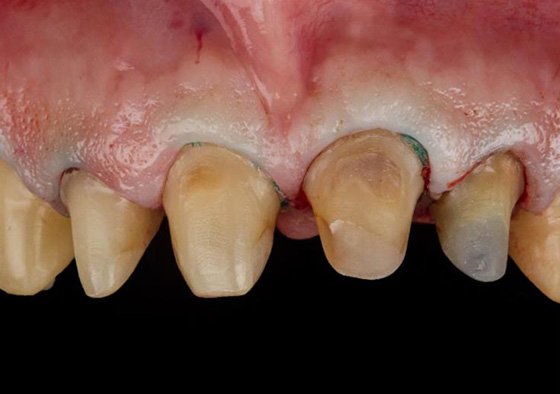

Composite core build-ups and completed teeth preparations with retraction cord and paste placement before final impression using 3M™ Filtek™ One Bulk Fill Restorative and 3M™ Astringent Retraction Paste.

Composite core buildups